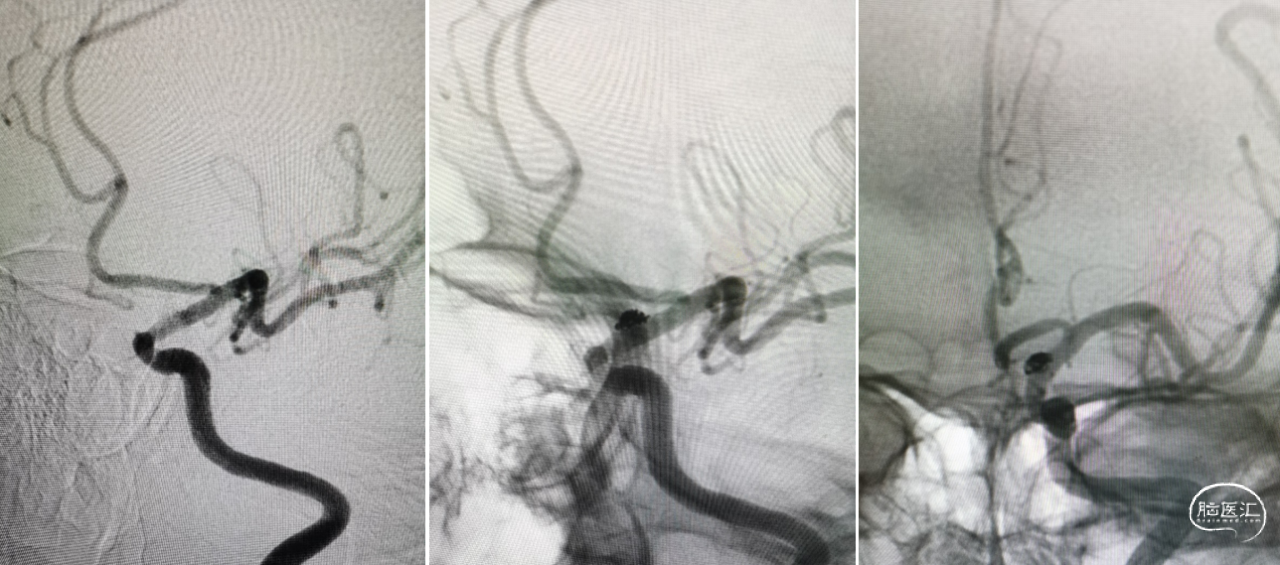

左侧颈内动脉床突上段动脉瘤,宽颈,5.7mm×3.6mm,考虑血泡样动脉瘤可能性大(左侧ICA造影)。

校正测量数据:载瘤动脉近、远端直径基本一致,为3.7mm左右。

充盈球囊精准释放支架,造影显示动脉瘤即刻不显影,脉络膜前动脉显影良好。

术前术后对比,动脉瘤消失,脉络膜前动脉保留完好。

动脉瘤不显影,血管各分支显影良好,支架打开良好。